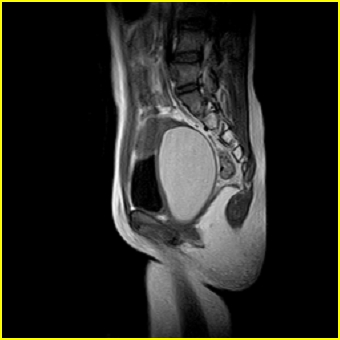

女、15岁、下腹疼痛2天,排尿困难1天。查体:处女膜闭锁,距处女膜约4至5cm处扪及一约5cm直径的圆形包块,张力较高,触痛明显、欠活动。b超提示子宫增大伴宫内增强回声团。

影像意见:子宫直肠陷凹积血。

更正影像意见:阴道积血。

处女膜闭锁,阴道积血

处女膜闭锁,阴道积血,子宫积血.

先天性处女膜闭锁,伴阴道积血,不除外先天性阴道粘液囊肿形成。

阴道积血,子宫积血.

子宫及阴道积血。

处女膜闭锁,伴子宫及阴道积血.